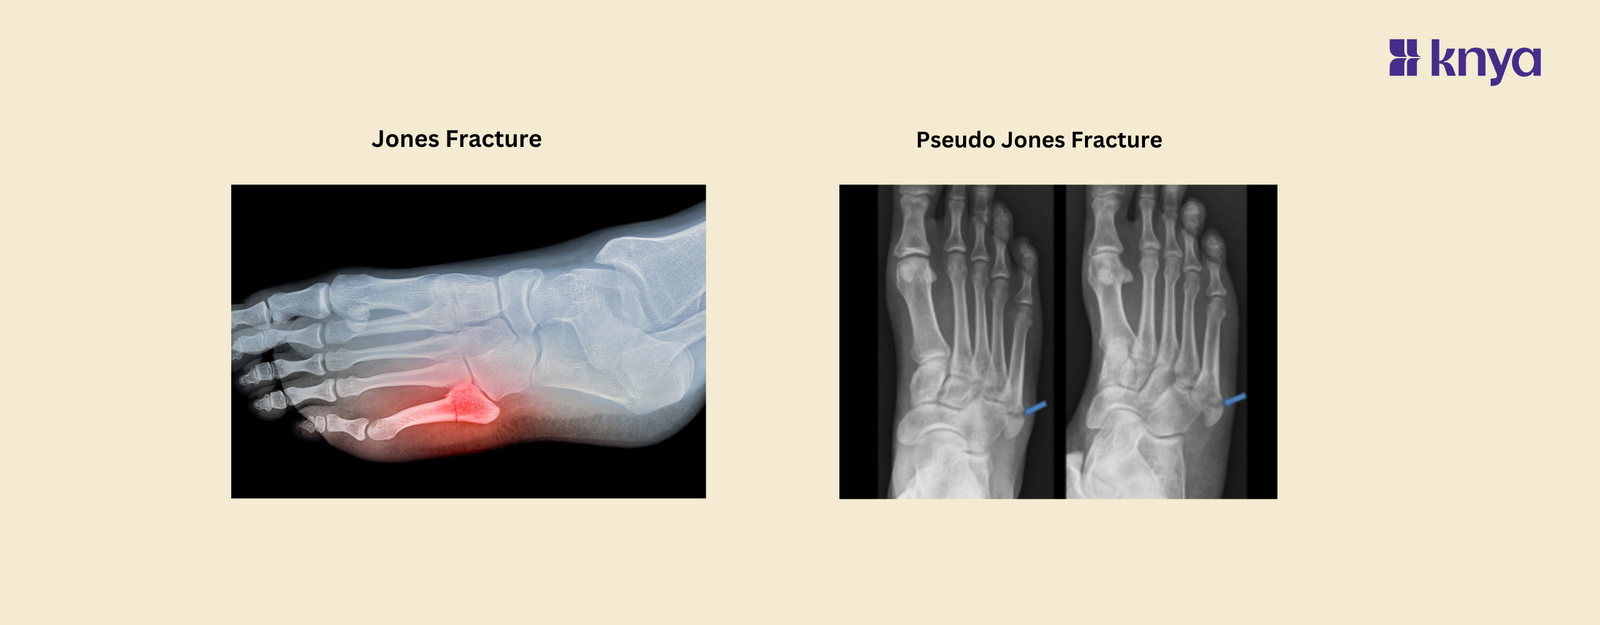

A Jones fracture occurs at the base of the fifth metatarsal bone, typically about 1.5 to 3 centimeters from the base of the bone where it connects to the midfoot. This specific location is critical because it is known to have a relatively poor blood supply, which can impede healing and increase the risk of complications.

Diagnosing a Jones fracture involves a physical examination and imaging studies such as X-rays. On X-ray, a Jones fracture appears as a fracture line at the base of the fifth metatarsal bone, often showing signs of displacement or separation.